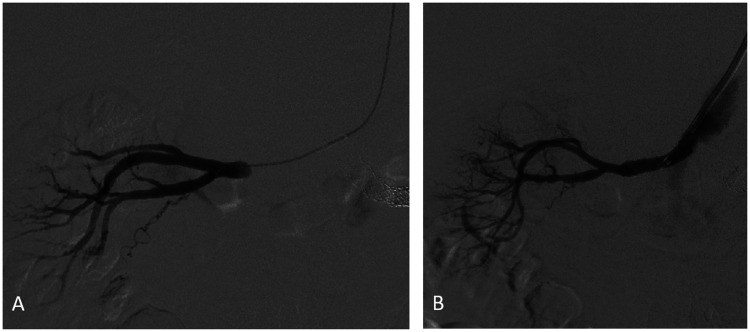

Case report: A 58-year-old male with a history of left renal artery stenosis and stent graft placement presented with symptoms of chest pain, shortness of breath, and flank pain. The patient was admitted to the Intensive Care Unit with the diagnosis of multiorgan failure and subsequent anuria that led to the initiation of hemodialysis. Computed tomography angiography demonstrated an aortic occlusion along with bilateral proximal renal artery occlusion with reconstitution of the mid to distal renal arteries via collateralization. The patient underwent angioplasty with bilateral renal artery stent-graft placement and successful revascularization of proximal renal arteries. Post-operatively, his renal function and urine output improved, and the patient was able to be weaned off hemodialysis along with the benefit of concurrent amelioration of his renovascular hypertension.

Conclusion: For select patients with renal artery occlusion, revascularization of the renal arteries may result in dialysis independence and stabilization of renovascular hypertension, despite prolonged time of ischemia.